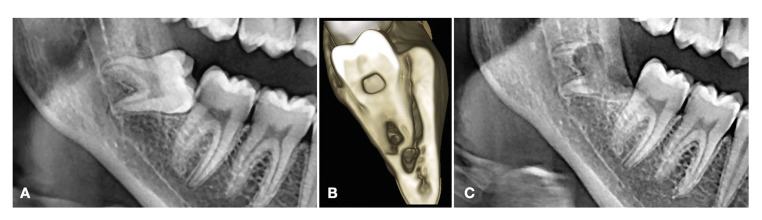

Material and methods: A retrospective case series evaluated the outcomes of coronectomies of impacted mandibular third molars. The inclusion criteria were: available preoperative, immediate postoperative and two-year panoramic radiographs, preoperative cone-beam computed tomography (CBCT), and a complete case history. The clinical evaluation comprised intraoperative complications (mobilized fragments of root and damage to adjacent structures), short-term complications (sensory alterations and postoperative infection), and long-term complications (infection or oral exposure). The IAN position with respect to the roots, root shape, eruption status, third molar position, radicular-complex migration and bone above roots were radiographically evaluated as well.

Results: Approximately a total of 2000 mandibular third molars were removed from 2011 to 2022. Of these, 39 molars in 34 patients were partially extracted using the coronectomy technique. The mean age was 36 years (range 22-77), and the mean follow-up was 28 months (range 24-84). There were two short-term postoperative infections. One of them was resolved through reintervention to remove the roots after antibiotic treatment, while the other required hospital admission and removal of the roots. One case of short-term transient lingual paresthesia was also recorded. Two long-term oral exposures were detected, and the root fragments had to be extracted. There were no permanent sensory alterations.